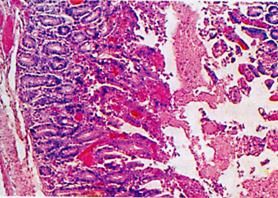

仔豬白痢腸道病變特徵大腸桿菌廣泛地存在於養豬環境中,如被糞便污染的地面、水源、飼料及其他物品中,經消化道吃進本菌,如在出生後很短時間內隨著吸吮母奶而吃進去。在正常條件下,這種腸道常在菌不表現致病作用,但在仔豬抵抗力減弱或消化機能障礙時,便可引起仔豬發病、下痢,以至敗血症而死亡。有的窩仔豬發病,有的窩發病少或不發病;同一窩仔豬發病也有先後,有輕有重,也有不發病者。

仔豬白痢腸道顯微結構病豬主要發生下痢,糞便為白色、灰白色或黃白色,粥樣、糊狀,有腥臭味。有時糞便中混有氣泡。病豬體溫一般不升高,精神尚好,到處跑動,有食慾。及時採取防治措施後常可治癒。如不及時採取處治措施,下痢可逐漸加劇,肛門周圍、尾及後肢常被稀糞沾污,仔豬精神委頓、食慾廢絕、消瘦、走路不穩、寒戰,喜鑽臥墊料或擠壓成堆。如並發肺炎則有咳嗽和呼吸加快。若治療不及時或治療不當,常經5~6天死亡。也有病期延長到2~3周以上的。病程較長而恢復的仔豬生長發育緩慢,甚至成為僵豬。總的說來,如能改善飼養管理,及時進行治療,預後是良好的。

仔豬白痢腸道病變根據本病發生特點、症狀、病理變化及結合飼養管理和衛生條件分析,容易做出診斷。流行病學特點:仔豬白痢大多發生在母豬飼養管理和衛生條件不良的養豬場,以10~20日齡的小豬發病最多,一窩仔豬中陸續發生或同時發生;一年四季均可發生,但在嚴冬及炎熱季節發生較多;每當氣候突然變壞時,發病數顯著增多。臨診症狀的特徵是排出白色、灰白色的粥狀糞便,有腥臭味。病理剖檢變化是胃腸卡他性炎症。必要時,需做細菌學檢查時。